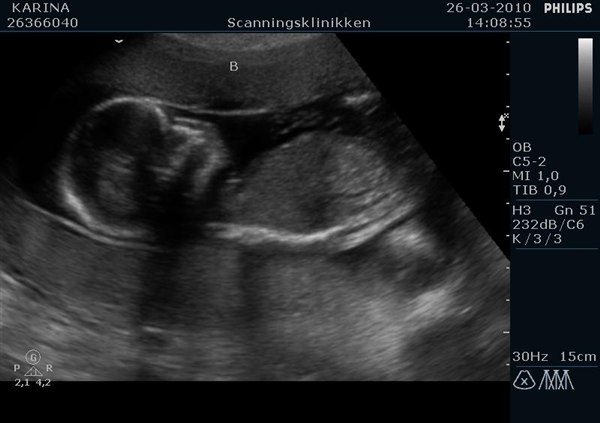

De første billeder er af deres ædler dele. Først fandt hun Viola. Efterfølgende søgt hun længe efter Alvin' s ædler dele. Lige da den var ved at være der, tog han hånden ned og rodede sig lidt i skridtet. Der var vi ikke i tvivl. Det var en dreng. Senere hen så var der næsten en lille tissemand på samtlige billeder. Han skulle bare lige finde ud af, at det var den vi ville se.

De sidste billeder er af de to i profil. Viola hedder A og Alvin hedder B.